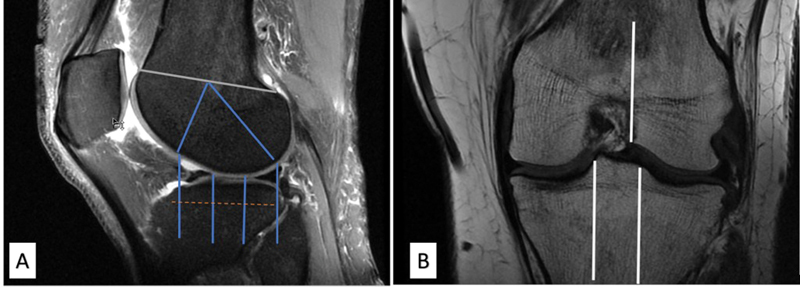

Background  Knee joint osteoarthritis (OA) is among the most prevalent degenerative diseases of the joints in the body. Various scoring system exists for grading OA, such as (1) magnetic resonance imaging (MRI) Osteoarthritis Knee Score (MOAKS), (2) clinical grading by Western Ontario and McMaster Universities Arthritis Index (WOMAC), and (3) X-ray grading of the Kellgren-Lawrence grading system (K-L). Objectives  To study MRI findings and MOAKS scoring of knee OA and correlation with WOMAC and K-L scoring. Setting and Design  Cross-sectional study in hospital population. Materials and Methods  A total 40 knee OA cases underwent an MRI of the knee. MOAKS scoring was done and compared with K-L grading and WOMAC scores. Statistical Analysis  Collected data were compiled systematically and interpreted using IBM SPSS statistics software 25.0. A p -value of less than 0.05 was considered significant. Results  The mean total WOMAC score was 9. K-L grade 2 was the most prevalent X-ray grade. Bone marrow lesion (BML) and cartilage loss in MOAKS score were greater in the medial femorotibial region. A moderate positive correlation was noted between the WOMAC score and K-L grade; full-thickness articular cartilage loss score at the medial femorotibial joint (MFTJ) and WOMAC score; partial-thickness articular cartilage loss score at lateral femorotibial joint (LFTJ) and WOMAC total pain score. No correlation was found between BML and pain severity score. Conclusion Higher WOMAC scores were associated with higher grades of K-L scoring and score of cartilage loss (partial and full thickness) of the MOAKS scoring system. The rest of the features of the MOAKS score (BML score, osteophyte, and synovitis) had no significant association with pain severity and K-L grading.

Abstract Image